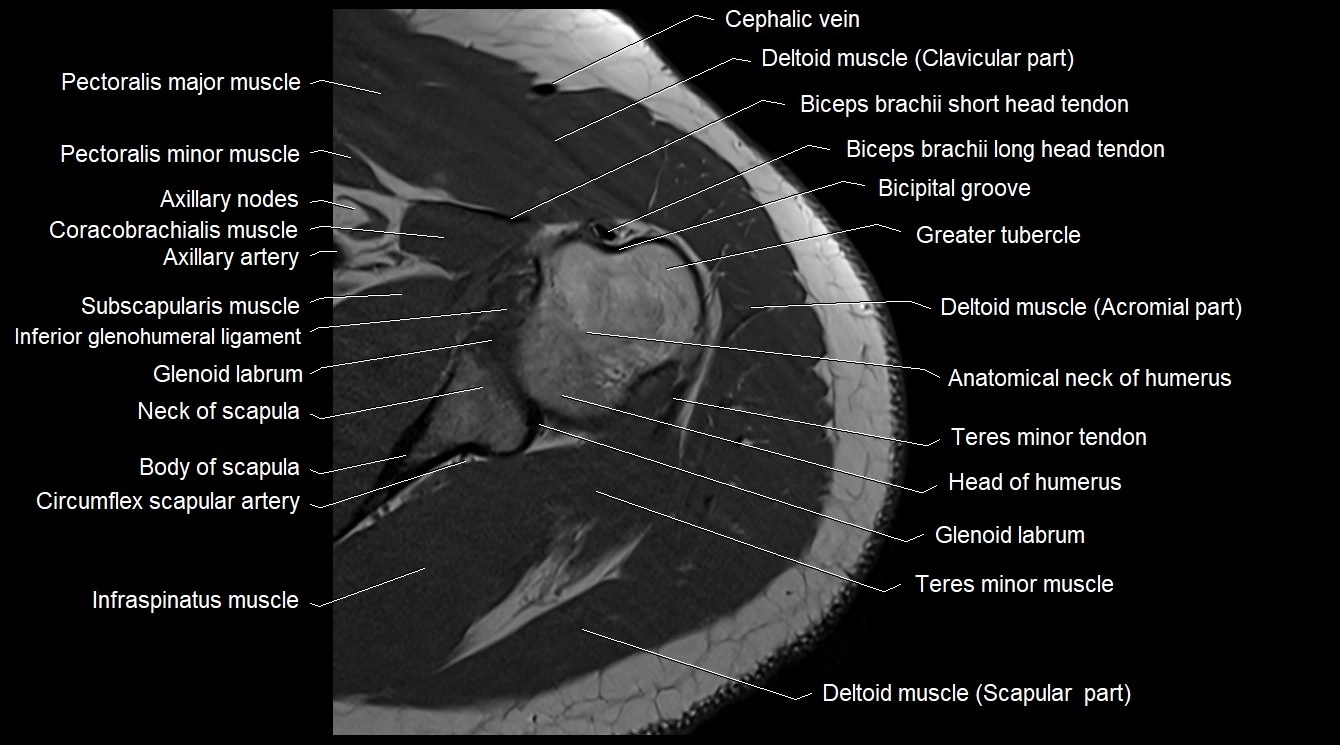

MRI image